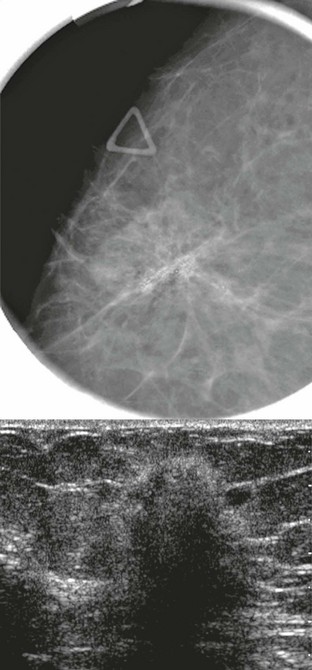

FIGURE 11-2 ILC.

A 49-year-old woman with a firm palpable lump in the right breast. Mammogram is normal in the palpable area that is marked by a triangle. US shows multiple hypoechoic areas with shadowing but no discrete mass, which is characteristic of ILC. (Reprinted with permission from Harvey JA. Unusual breast cancers: Useful clues to expanding the differential diagnosis. Radiology 2007;242:683-694.)